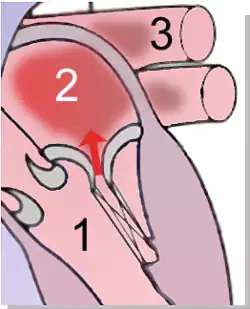

Insuffisance mitrale

1. Valve mitrale — 2. Ventricule gauche — 3. Atrium gauche — 4. Aorte

L'insuffisance mitrale (ou fuite mitrale ou régurgitation mitrale) est une des maladies les plus fréquentes parmi les pathologies des valves cardiaques chez l'humain et quelques autres espèces animales. Il s'agit d'une dysfonction de la valve mitrale consistant en un défaut de coaptation des deux feuillets de cette dernière, entraînant un reflux de sang du ventricule gauche dans l'atrium gauche pendant la phase d'expulsion du sang (systole) (voir schéma), au lieu d'aller dans l'aorte.

L'ombre au bout de la flèche rouge symbolise le reflux sanguin

1 Ventricule gauche — 2 Atrium gauche